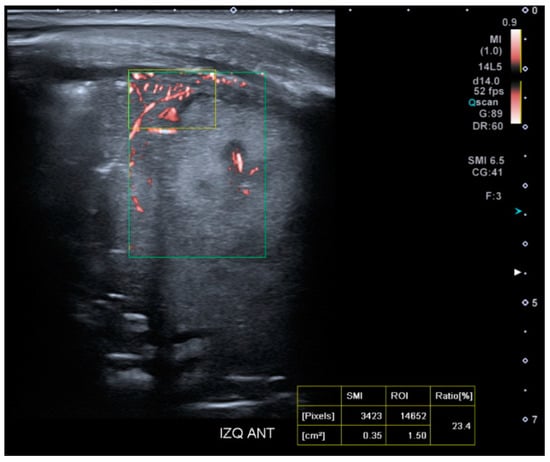

2.4.3. Superb Microvascular Imaging Acquisition

For the study of tissue microvascularization, the transducer will be kept perpendicular to the skin, using the same intercostal window without modifying the patient’s position. The microvascularization ratio measurement will be performed using SMI within the colored box previously defined for lung SWE measurement (Figure 4). The SMI Doppler mode will be activated, along with the ‘Vascular Index’ tool, selecting a velocity scale of 0.9 m/s. A rectangular ROI (15 × 10 mm) will be selected at a maximum depth of 5 cm. Microvascularization results will be expressed as a percentage.

Figure 4. Presentation interface of the SMI mode on the Aplio A500 device (Canon™).